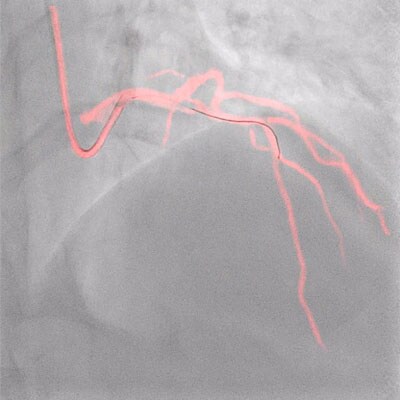

Wenn Sie ein bildgeführtes Verfahren durchführen, brauchen Sie eine zuverlässige Bildqualität – immer und zu jeder Zeit. AlluraClarity mit Philips ClarityIQ bietet Ihnen diese Bildqualität bei einer niedrigen Strahlendosis. In mittlerweile 18 klinischen „peer reviewed“ Studien weltweit wurde klar gezeigt: Mit dieser Technologie lässt sich eine 50-80% niedrigere Strahlendoses erreichen, und zwar bereichs-, patienten- und anwenderübergreifend*. Wir haben spontane Reaktionen aus der interventionellen Neuroradiologie, interventionellen Kardiologie, interventionellen Onkologie und Gefäßchirurgie gesammelt. Sie bestätigen uns, dass unsere Technologie bildgeführte Verfahren vereinfacht, das Dosismanagement für Patienten und Personal verbessert und die Zuverlässigkeit steigt.